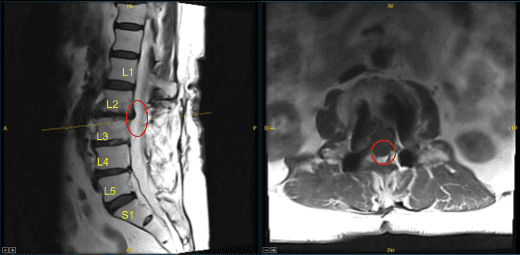

This patient had previously undergone an instrumented arthrodesis at an outside facility at L3-5. They presented with right anterior thigh and left posterior leg pain. Imaging displayed adjacent segment degeneration above and below her fusion mass which correlated well with her symptoms.